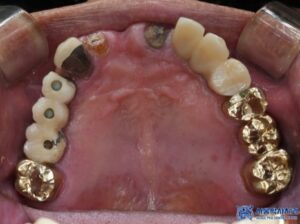

위 환자분은 앞니가 많이 불편해서

임플란트 치료를 고민하고 계셨는데요.

치아를 확인해보니 앞니 두 개는

치아의 뿌리 부분만 남아 있었고,

심한 치주염과 충치로 인해

유지하기 어려운 상태였습니다.